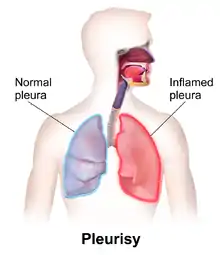

Pleurisy, also known as pleuritis, is inflammation of the membranes that surround the lungs and line the chest cavity (pleurae).[1] This can result in a sharp chest pain while breathing.[1] Occasionally the pain may be a constant dull ache.[5] Other symptoms may include shortness of breath, cough, fever, or weight loss, depending on the underlying cause.[5] Pleurisy can be caused by a variety of conditions, including viral or bacterial infections, autoimmune disorders, and pulmonary embolism.

Pleurisy is often associated with complications that affect the pleural space.

Pleural effusion

In some cases of pleurisy, excess fluid builds up in the pleural space. This is called a pleural effusion. The buildup of excess fluid, will more often than not force the two layers of the pleura apart so they don't rub against each other when breathing. This can relieve the pain of pleurisy. A large amount of fluid can result in collapse of the lung. This can make it difficult to breathe.

A doctor uses a stethoscope to listen to the breathing. This method detects any unusual sounds in the lungs. A person with pleurisy may have inflamed layers of the pleurae that make a rough, scratchy sound as they rub against each other during breathing. This is called pleural friction rub.